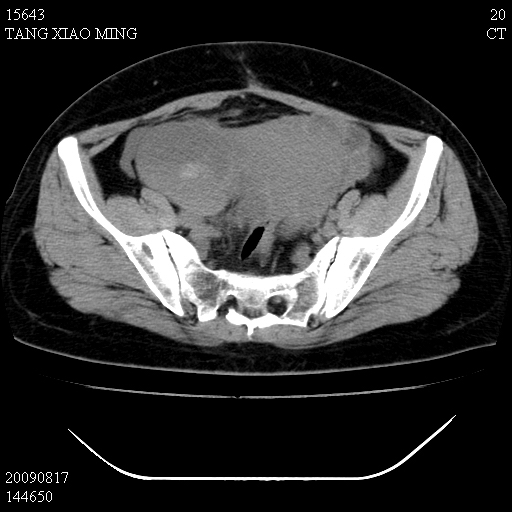

标题: CT21692:盆腔病变

女,33岁,右下腹痛2年余,既往宫外孕病史,如在我院手术,结果下周公布,

可能的诊断。1子宫内膜异位【子宫腺肌症并右卵巢巧克力囊肿】;2 右卵巢囊腺瘤。子宫肌瘤

1)考虑卵巢巧克力囊肿,不排除卵巢囊腺瘤。2)子宫肌瘤可能。

卵巢囊腺瘤,子宫肌瘤,直肠壁厚,不除外占位.